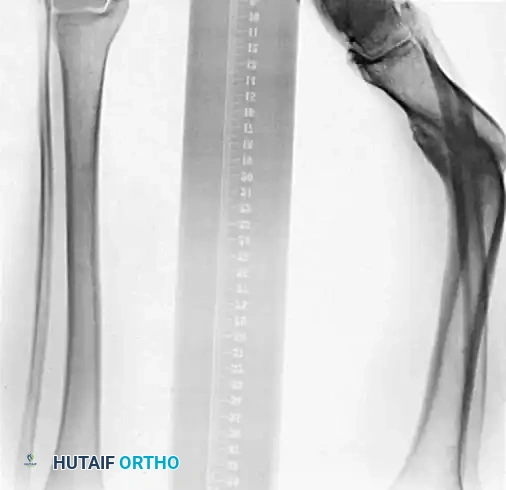

Preoperative planning requires precise determination of the angular deformity, rotational malalignment, leg-length discrepancy, and translation.

Angular deformities in the frontal (varus-valgus) and sagittal (flexion-extension) planes can be mathematically resolved into a single uniplanar deformity in an oblique plane. The degree of maximal deformity is always greater than the angular measurements seen on standard orthogonal anteroposterior (AP) or lateral radiographs.

Rotational deformity is best evaluated with a computed tomography (CT) scan measuring the tibial torsion angle, or clinically by measuring the transmalleolar axis relative to the tibial tubercle. Sangeorzan et al. developed a highly effective mathematical model for planning oblique osteotomies that simultaneously correct angular and rotational deformities while allowing for axial lengthening.

Fig. 2: Preoperative templating and mathematical modeling of a multiplanar tibial deformity, identifying the plane of maximal angulation.